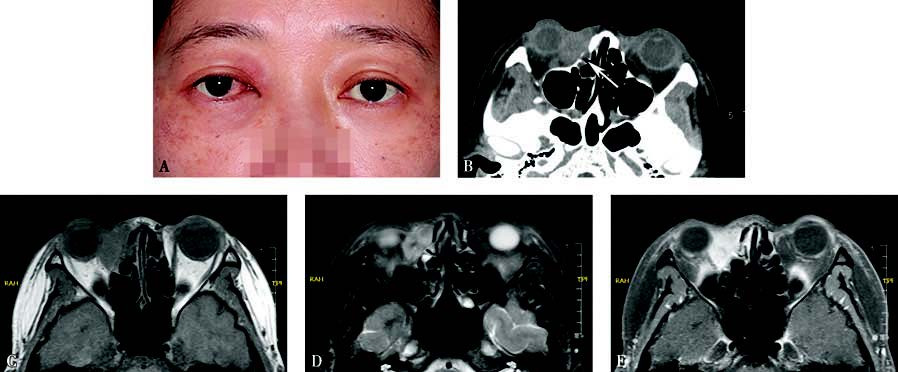

Figure 1 Appearance and imaging of a patient with right lacrimal sac squamous carcinoma

A. The patient presents with epiphora in the right eye, conjunctival congestion, a medial canthal mass, and proptosis.

B. Axial CT shows an irregular mass in the lacrimal sac region with poorly defined margins and significant destruction of surrounding bone (white arrow).

C. Axial T1-weighted MRI shows the tumor with intermediate to low signals.

D. Axial T2-weighted MRI shows the tumor with inhomogeneous intermediate to high signals.

E. Contrast-enhanced axial T1-weighted MRI indicates significant tumor enhancement.